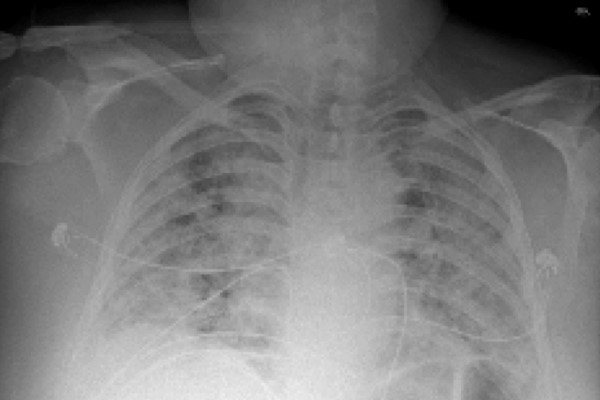

U analizi podataka o pacijenatima s teškom upalom pluća i respiratornim zatajenjem korišten je pristup strojnog učenja zvan CarpeDiem koji bolesne grupira na temelju elektroničkog zdravstvenog kartona